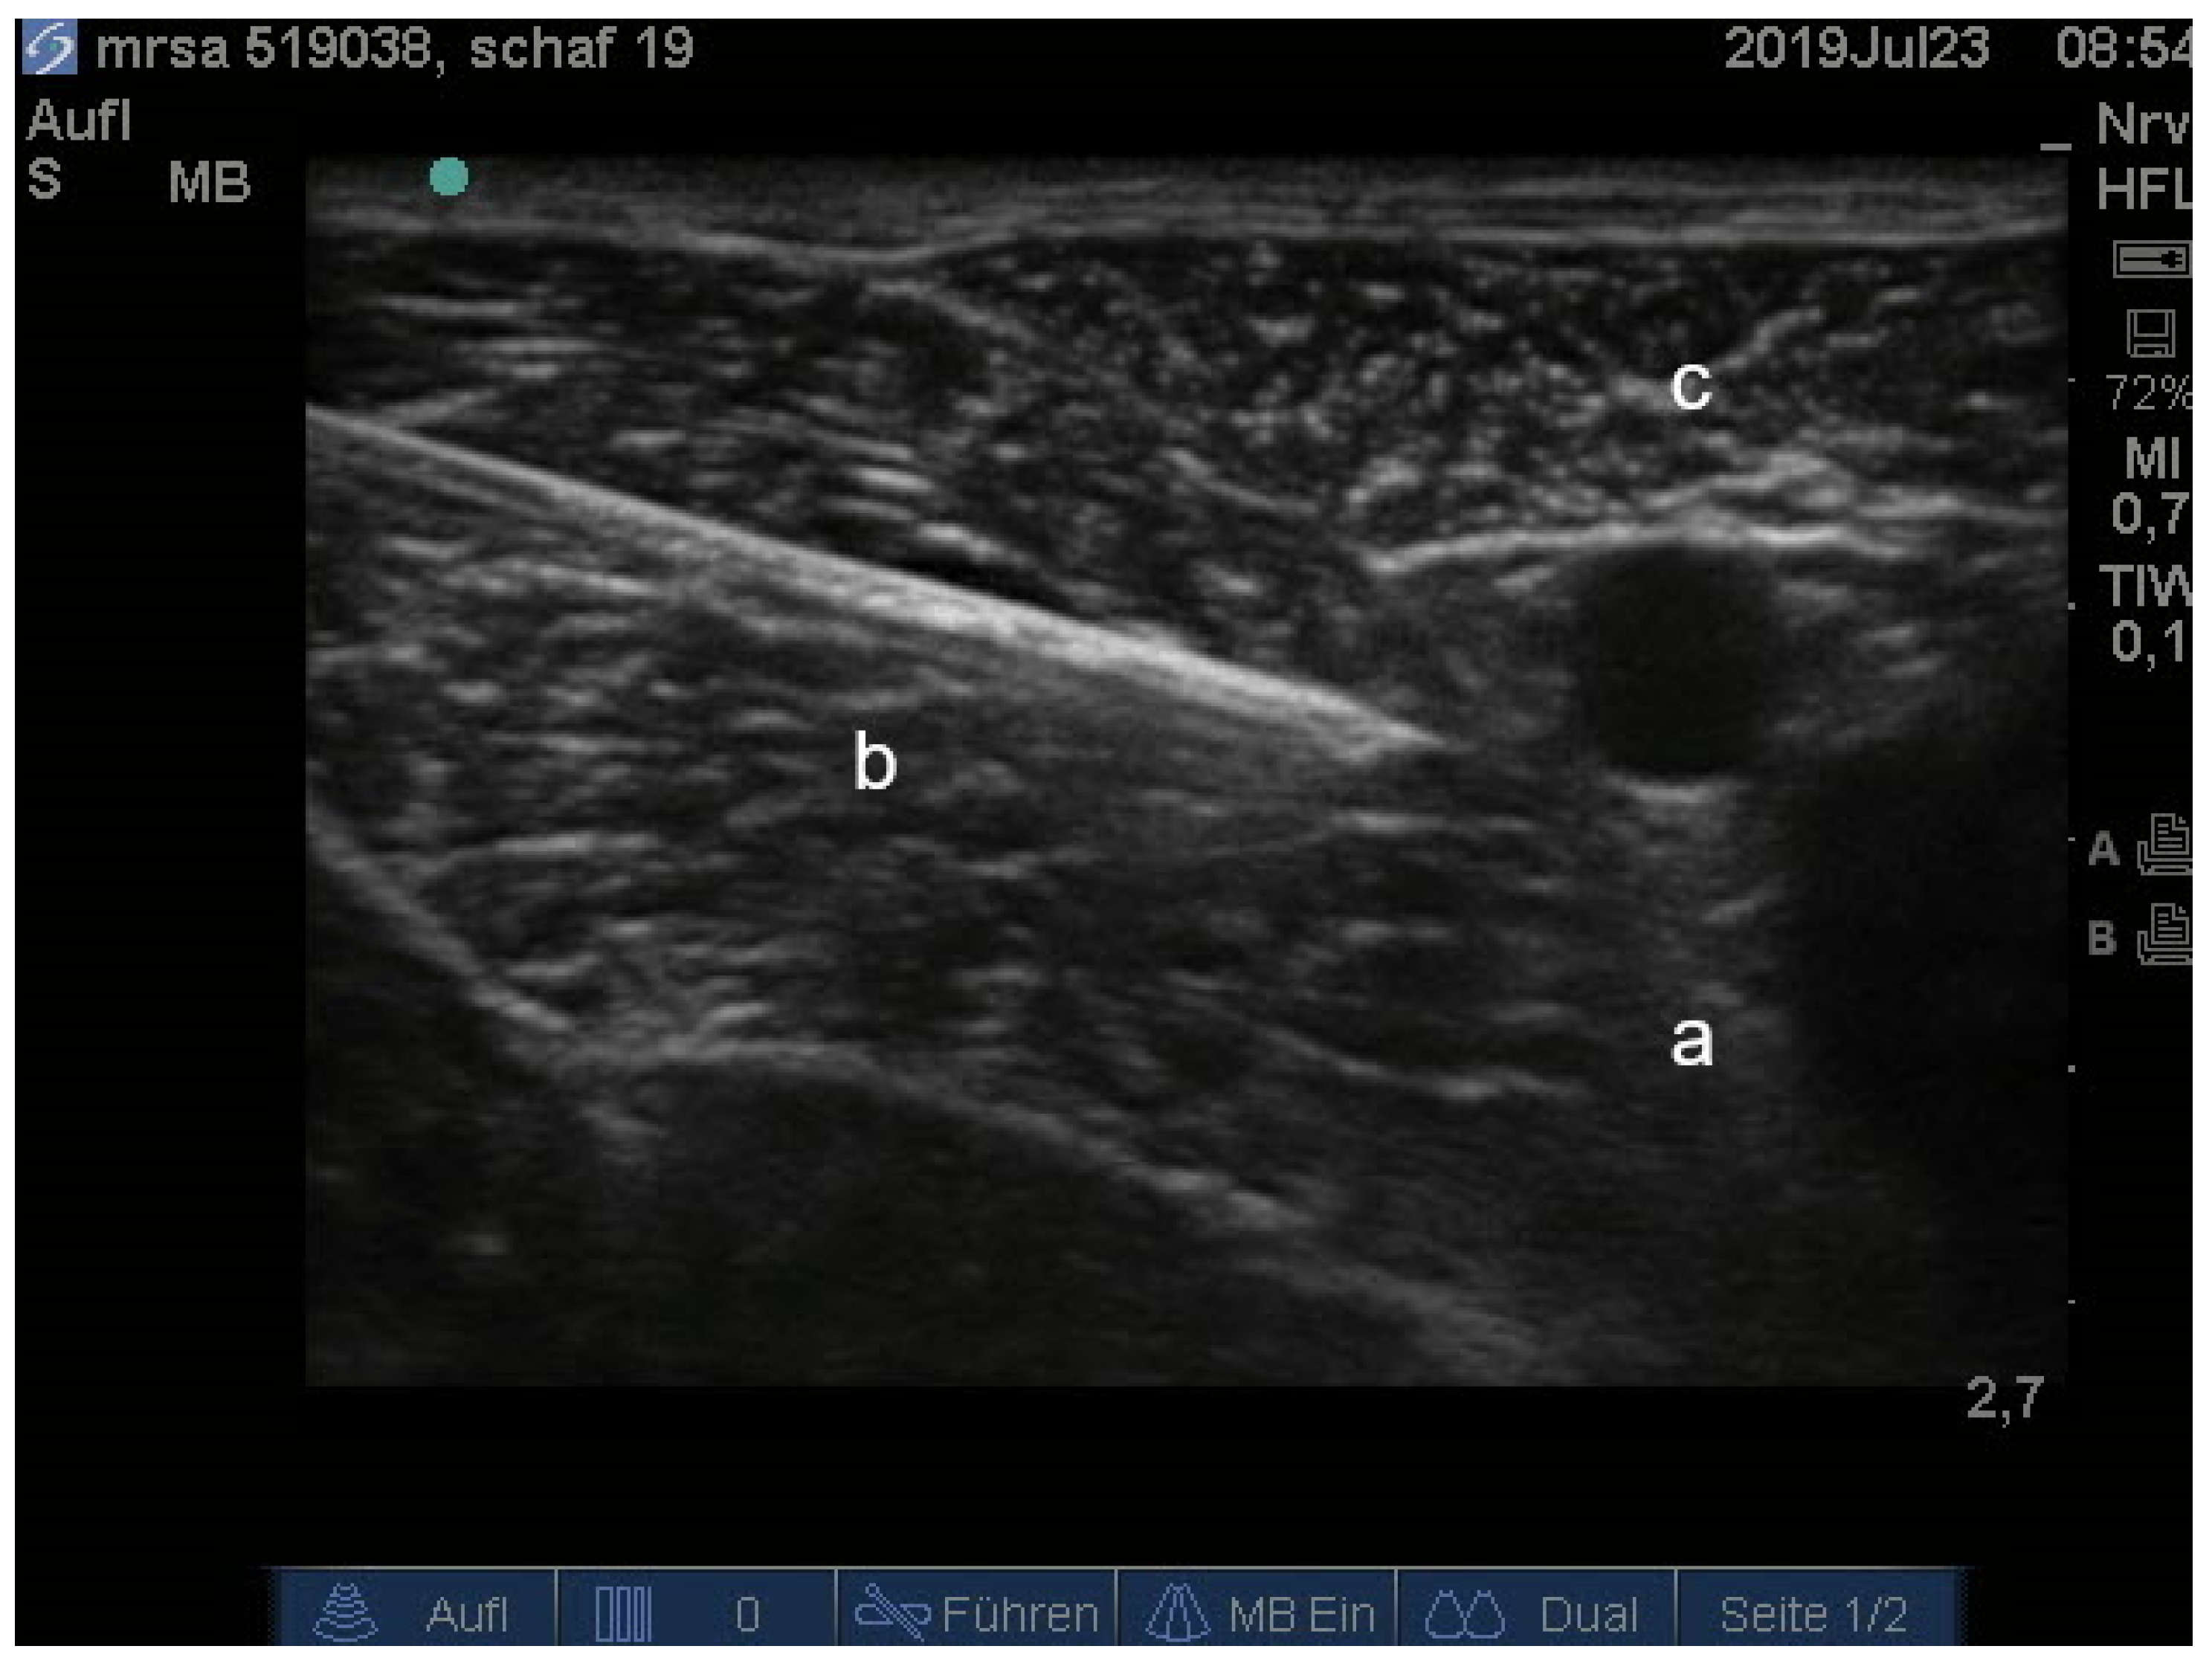

- Waag, S.; Stoffel, M.H.; Spadavecchia, C.; Eichenberger, U.; Rohrbach, H. Ultrasound-guided block of sciatic and femoral nerves: An anatomical study. Lab. Anim. 2014, 48, 97–104. [Google Scholar] [CrossRef]